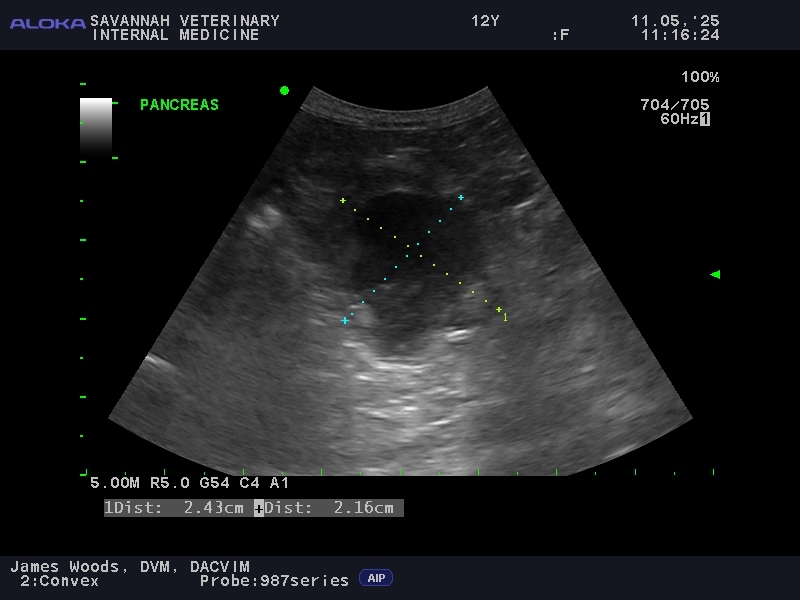

Visualizing The Pancreas: For the diagnosis of feline pancreatitis, an abdominal ultrasound is an important diagnostic tool. While X-rays are typically not very useful, ultrasound provides a non-invasive way to visualize the pancreas. The accuracy of ultrasound is highly dependent on the skill of the operator, as the pancreas can be difficult to locate and assess in cats. At Savannah Veterinary Internal Medicine, our team performs detailed ultrasounds to help identify pancreatitis, even in subtle cases. Even more so than the fPLI test, ultrasound may be normal in cats with mild, or chronic pancreatitis.

To illustrate this diagnostic challenge, the appearance of the pancreas on ultrasound varies significantly between different forms of the disease:

Acute vs. Chronic Feline Pancreatitis Ultrasound Images:

Recognize the varied imaging features of the inflamed feline pancreas, where acute and chronic forms present with distinct ultrasonographic changes.